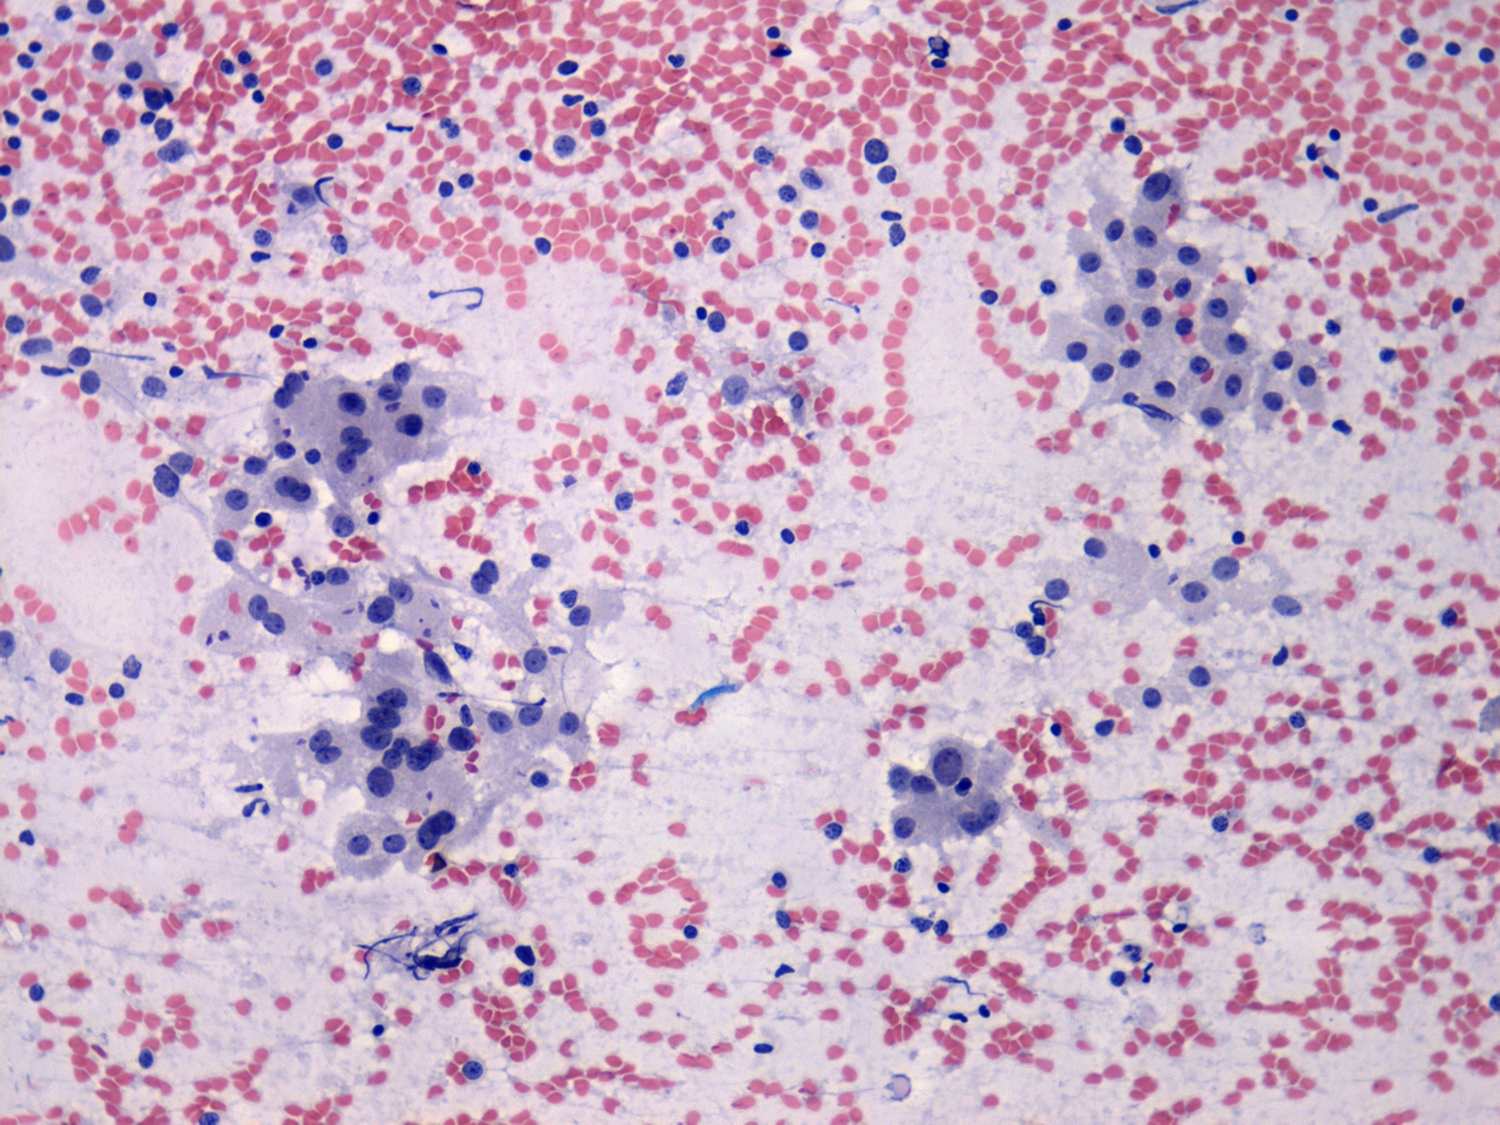

Chronic lymphocytic thyroiditis - Case 33. (cytologic picture 2)

Pap-smear, 200x. Lymphoid cells mixed with compact clusters of thyrocytes.